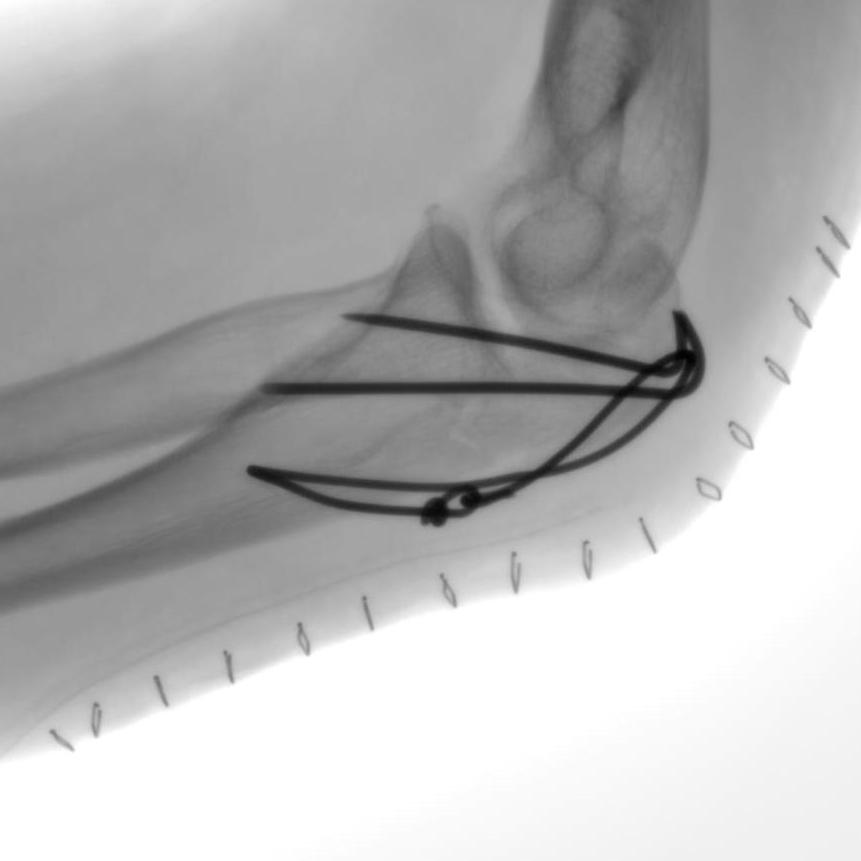

Мобильная рентгеновская С-дуга «Сапфир»

| «Сапфир» — новая мобильная С-дуга производства АО «МТЛ», предназначенная для точной диагностики во время хирургических вмешательств. Режимы работы: рентгеноскопия, рентгенография, цифровая субтракционная ангиография. | Компактная конструкция и удобное управление делают систему универсальным инструментом для операционных различного профиля, позволяя проводить как рутинные, так и специализированные процедуры. Подходит для широкого спектра исследований и хирургических вмешательств под рентгеновским контролем, включая травматологию, ортопедию, урологию, общую хирургию и обследование периферических сосудов. |

Высокое качество визуализации